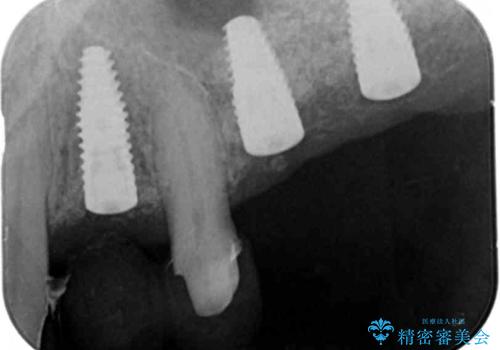

骨の造成を行った上顎インプラント治療

精密検査の結果、重度の歯周病が認められ大きな骨の吸収を認めました。

予後の悪く保存の難しい歯を抜去し、骨の造成を含んだインプラント治療を計画します。

骨の造成を行ったことで歯肉のラインは平らになり、清掃性の高い歯周環境を作り出すことができました。